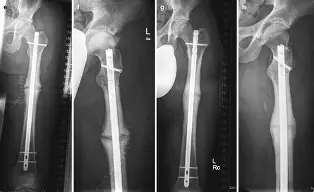

4. Femur Gap Nonunion in a Child Explained by Prof. Dr. Anil Dhal

A rare and important case discussion.

Key takeaways:

• Understanding pediatric gap nonunion

• How it differs from adult cases

• Clinical approach and management

• Surgical planning principles

• Clinical insight: Early diagnosis and proper planning make a significant difference in outcomes.